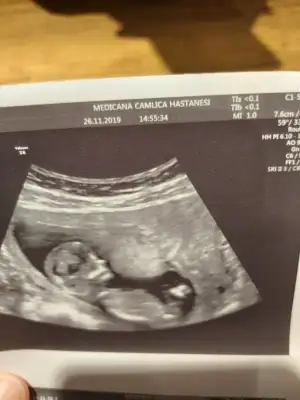

Ama o nub çıkıntısı değil ayak sankiBunu ben bile anladım bu erkek![]()

Öğrendiniz mi neymiş ben genelde kıza benzetiyorum nedenseBenim de kız demiştiniz![]()